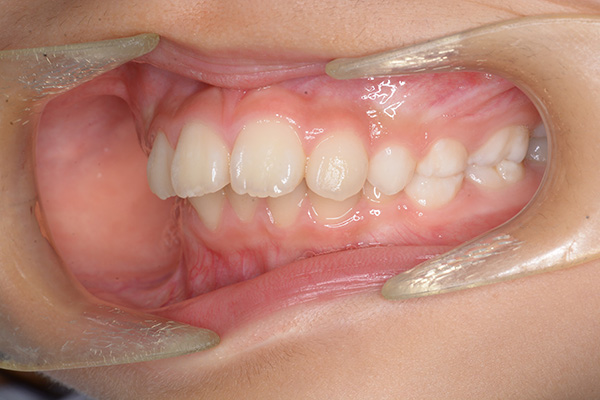

動的治療終了時

FP・IOP

批評・予后 本来であれば永久歯歯列完成後に本格矯正治療を行って良い症例だが、患者さん(保護者)の強い希望から早期治療にて改善を行った症例である。バイオネーターを夜間就寝中に使用して咬合誘導を行った結果、前歯の前突感は解消され比較的緊密な咬合は得られたように思う。